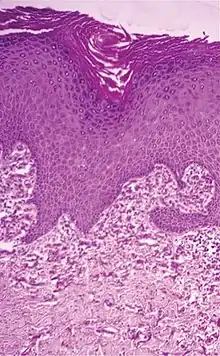

Elastosis perforans serpiginosa Degenerated elastic fibers and transepidermal perforating canals (arrow in image points at one of them)[11]